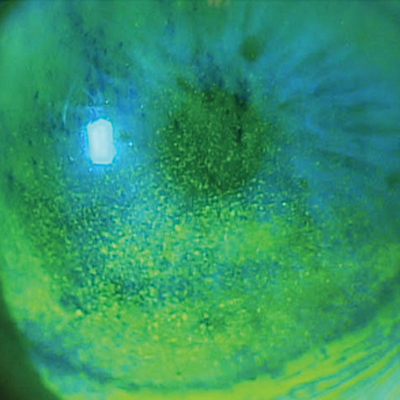

“The proper management of ocular surface disease (OSD) is a cornerstone for successful anterior segment surgery and overall ocular health,” said Chief Medical Editor Sumit “Sam” Garg, MD, introducing this special bonus issue on dry eye and ocular surface disease.